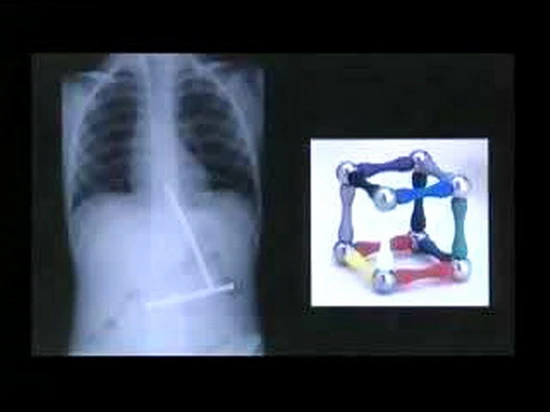

Phim chụp X_quang này cho thấy cậu bé đã nuốt những thanh nam châm rời nhau của một khối hình. Khi các bác sĩ phẫu thuật thì các thanh nam châm đã ghép lại với nhau.